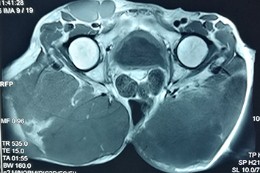

患者术前影像资料